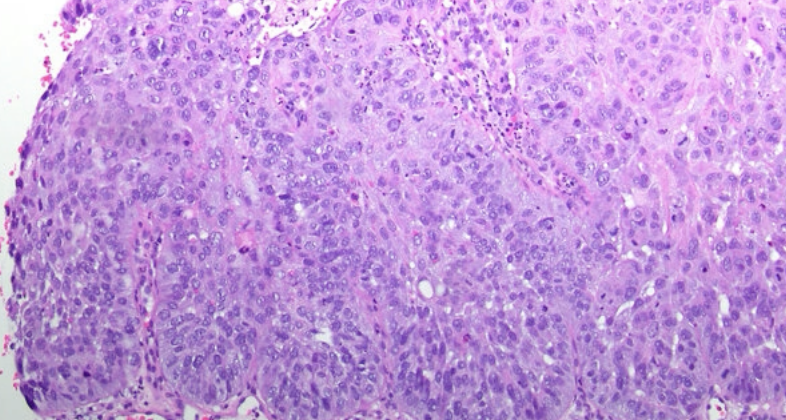

Sever

Oral Squamous Cell Carcunoma(OSCC)

分級

根據和正常上皮的相似度及產生的 keratin 多寡來分級

- Grade I, well-differentiated: 產生正常量的 keratin

- Grade II, moderately-differentiated: 產生少量的 keratin

- Grade III, poorly-differentiated: 幾乎不產生 keratin

Grading 的判斷較為主觀,staging 和預後(prognosis)的相關性比 grading 高很多。